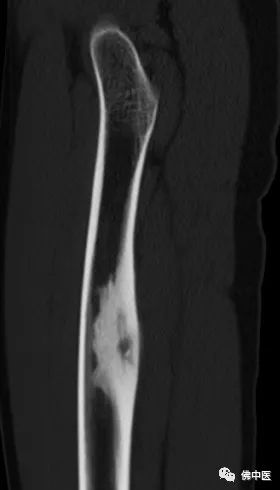

小陆右腿检查片

小陆病灶所在分布有重要的神经血管

经诊断,小陆同样患有骨样骨瘤。据其主治医生潘海文介绍,经影像学检查,病灶位于大腿中上段内后方,大腿内后方分布有重要的神经血管,加上瘤巢细小,直径仅约7毫米,术中探查犹如大海捞针。